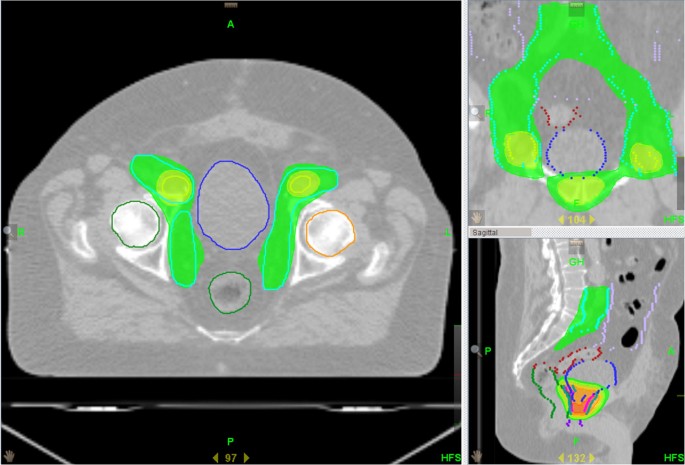

Salvage nodal radiation therapy is typically applied to patients who have already undergone radiotherapy in the past, for whom the recurrence of cancer within the lymph nodes signifies an evolving clinical scenario. The treatment involves several advanced techniques, each designed to maximize targeting accuracy while mitigating the risk to non-cancerous tissues.

The major methods used in SNRT include:

• Volumetric Modulated Arc Therapy (VMAT)

• Intensity-Modulated Radiation Therapy (IMRT)

• Stereotactic Body Radiation Therapy (SBRT)

• Intensity-Modulated Proton Therapy (IMPT)

Each method comes with its own set of subtle details and a range of considerations that the treating physician must weigh carefully. When these technologies are used in conjunction with PET imaging findings, the resulting treatment plan is finely tuned to offer the best possible outcomes. In many ways, SNRT represents a marriage between cutting-edge technology and a nuanced understanding of prostate cancer behavior, providing hope for those whose treatment options were previously limited.